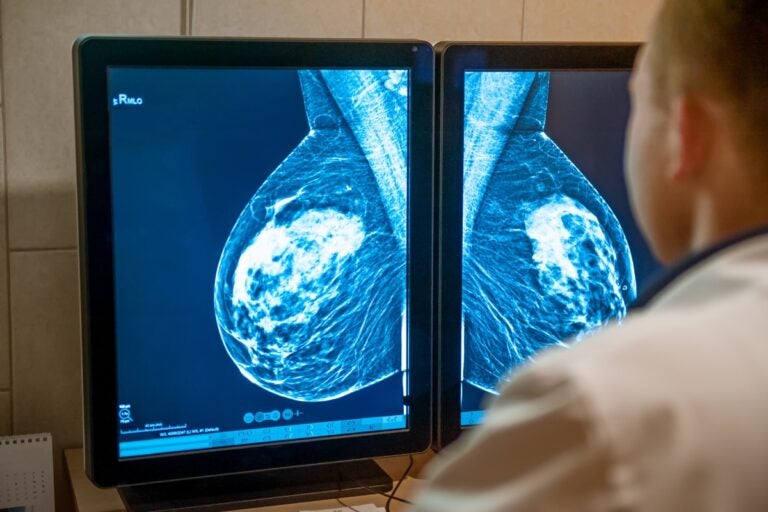

Penn Researchers offer hope thanks to a major discovery on how to identify so-called cancer sleeper cells. Are we getting closer to a cure?

The Breast Cancer Program at the University of Pennsylvania’s Abramson Cancer Center is pioneering research to understand and detect so-called dormant “sleeping” cancer cells that can later reactivate and lead to metastasis. Clinical trials, currently underway, are targeting these cells, many of which are found in the bone marrow, where they can be monitored and attacked.